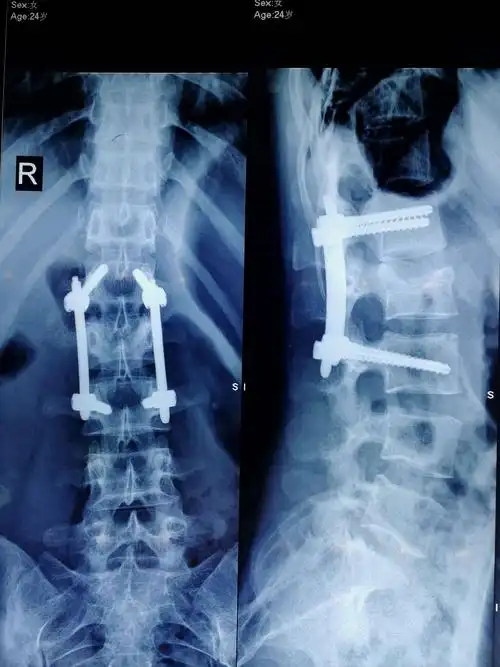

胸腰椎骨折后路复位内固定术――曲阳第三医院骨科